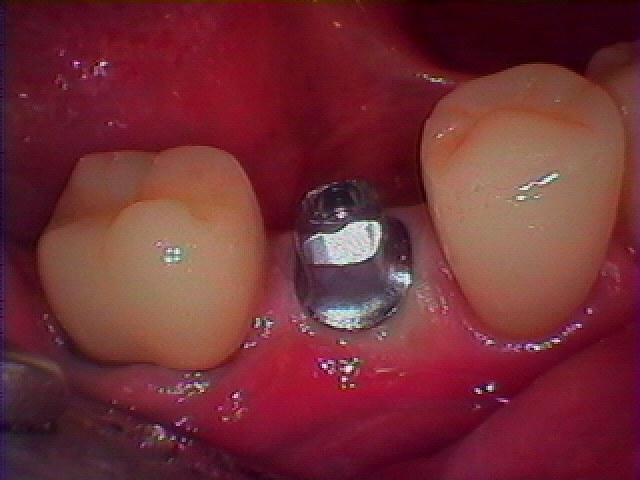

埋入時になります

2か月待つとこのように綺麗に治癒します

カスタムのアバットメントを建てていきます